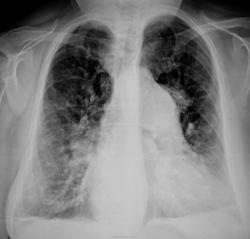

Ну, что тут можно сказать. Очевидна артериальная гипертензия в малом круге. Вследствие чего? Скорее всго вследствие выраженного двустроннего пневмофиброза, на КТ могли бы выявить идиолпатический легочный фиброз. А что там, у 2-дуги, "черненькое теменеется, беленькое белеется", бог весть; может что-то нестрашное, например, компрессия.

В целом согласен. Тут очень важная информация может быть добыта из снимков прошлых лет. Но правый корень смотрится как-то не очень типично для лёгочной гипертензии: лишний шарик. Томографировать надо

Левый контур сердца "тянет" на сердечный порок, изменения в легких могут быть обусловлены именно этой патологией.

Застой и версия порока очень правдоподобна. Есть анамнез?

Вероятно - септальный врожденный порок - дефект межжелудочковой перегородки или незаращенный Баталлов проток. Выраженная артериальная легочная гипертензия и маленькая аорта из-за сброса слева направо. Пневмофиброз и эмфизема.

Не многовато пневмофиброза для ВПС? Хотя изображения, конечно, не Айс).